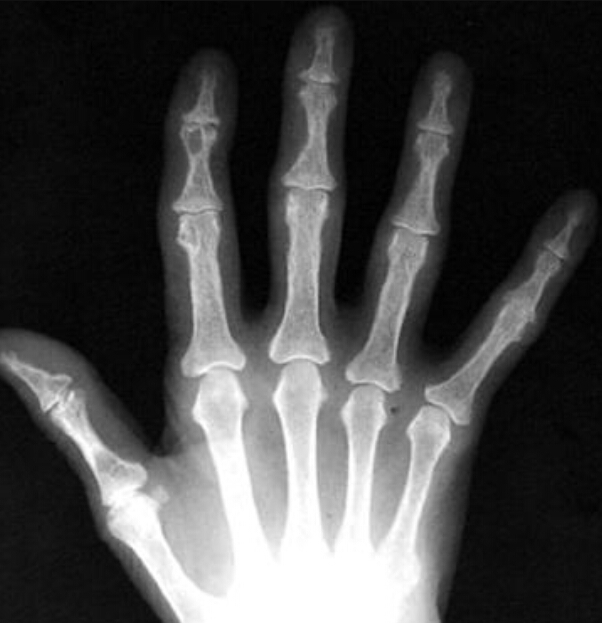

What is the radiographic feature? This is the most definitive radiographic sign of what disease?

subperiosteal resorption, HPT